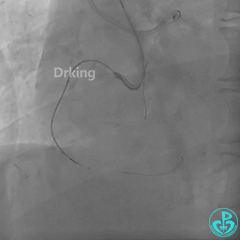

手术策略:

右冠无明显入路且迂曲钙化,正向操作进入内膜下可能性大,逆向条件一般但可以尝试,综合考虑,设想前向进入内膜下,采用S-ADR术式可快速高效开通右冠CTO。

AL1,微导管辅助下XTA、P200导丝无法前行,感觉近段纤维帽坚硬。

导丝怎么扩收藏:器械难以通过的CTO病变之技术图谱_https://www.jmylbn.com_新闻资讯_第9张